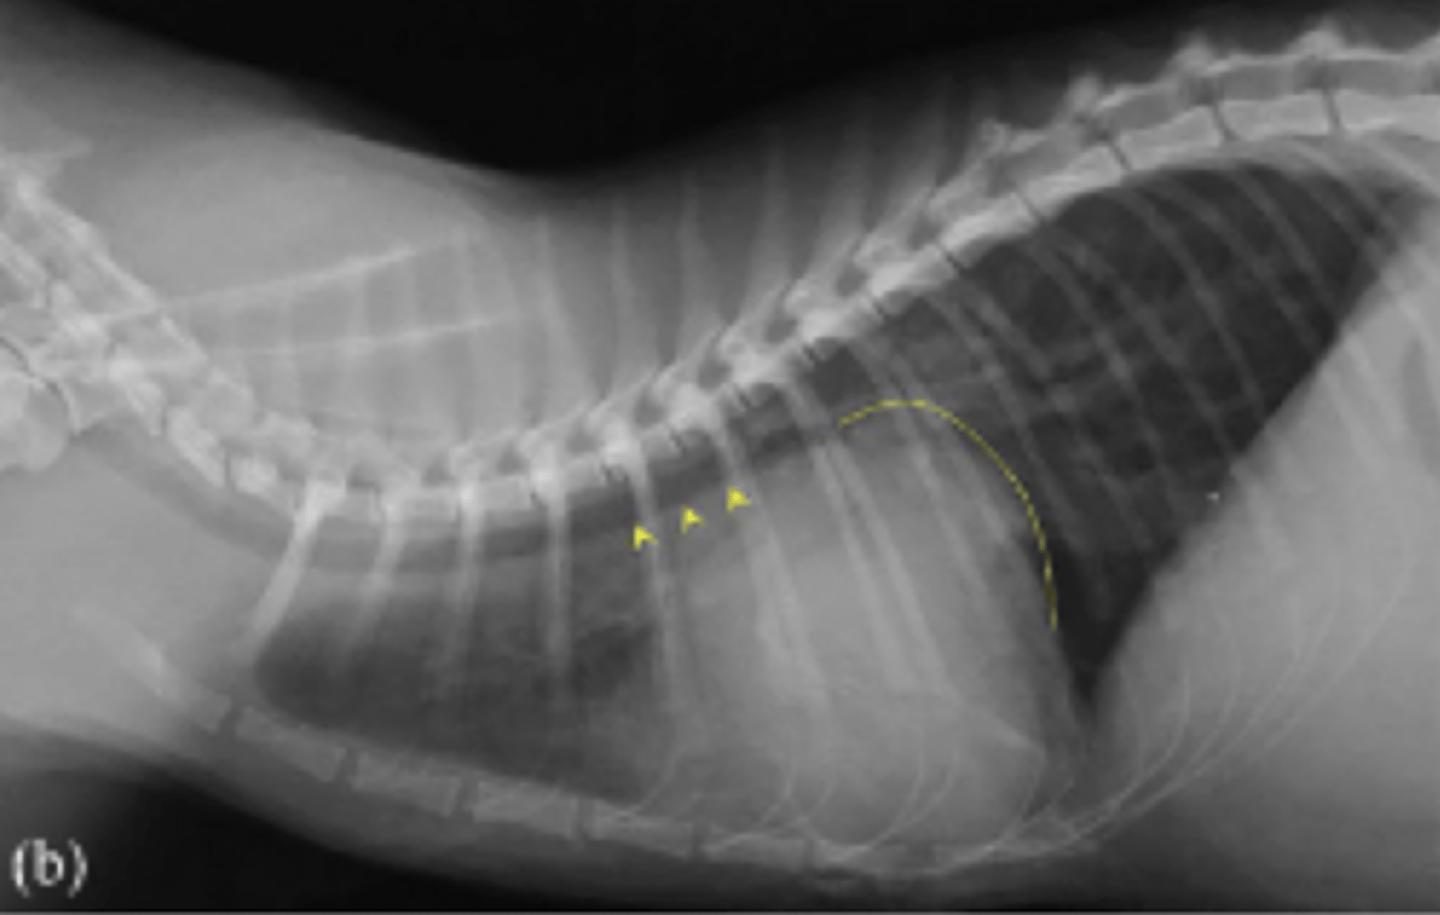

torsión esplénica

(C invertida)

patología: